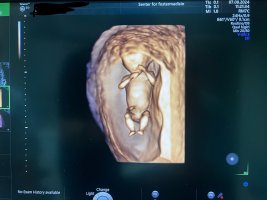

Så morro med 3DTUL idag, ble flytta fra 13+0 til 13+3Fikk ikke sett kjønn, men alt så helt perfekt ut!

![]()